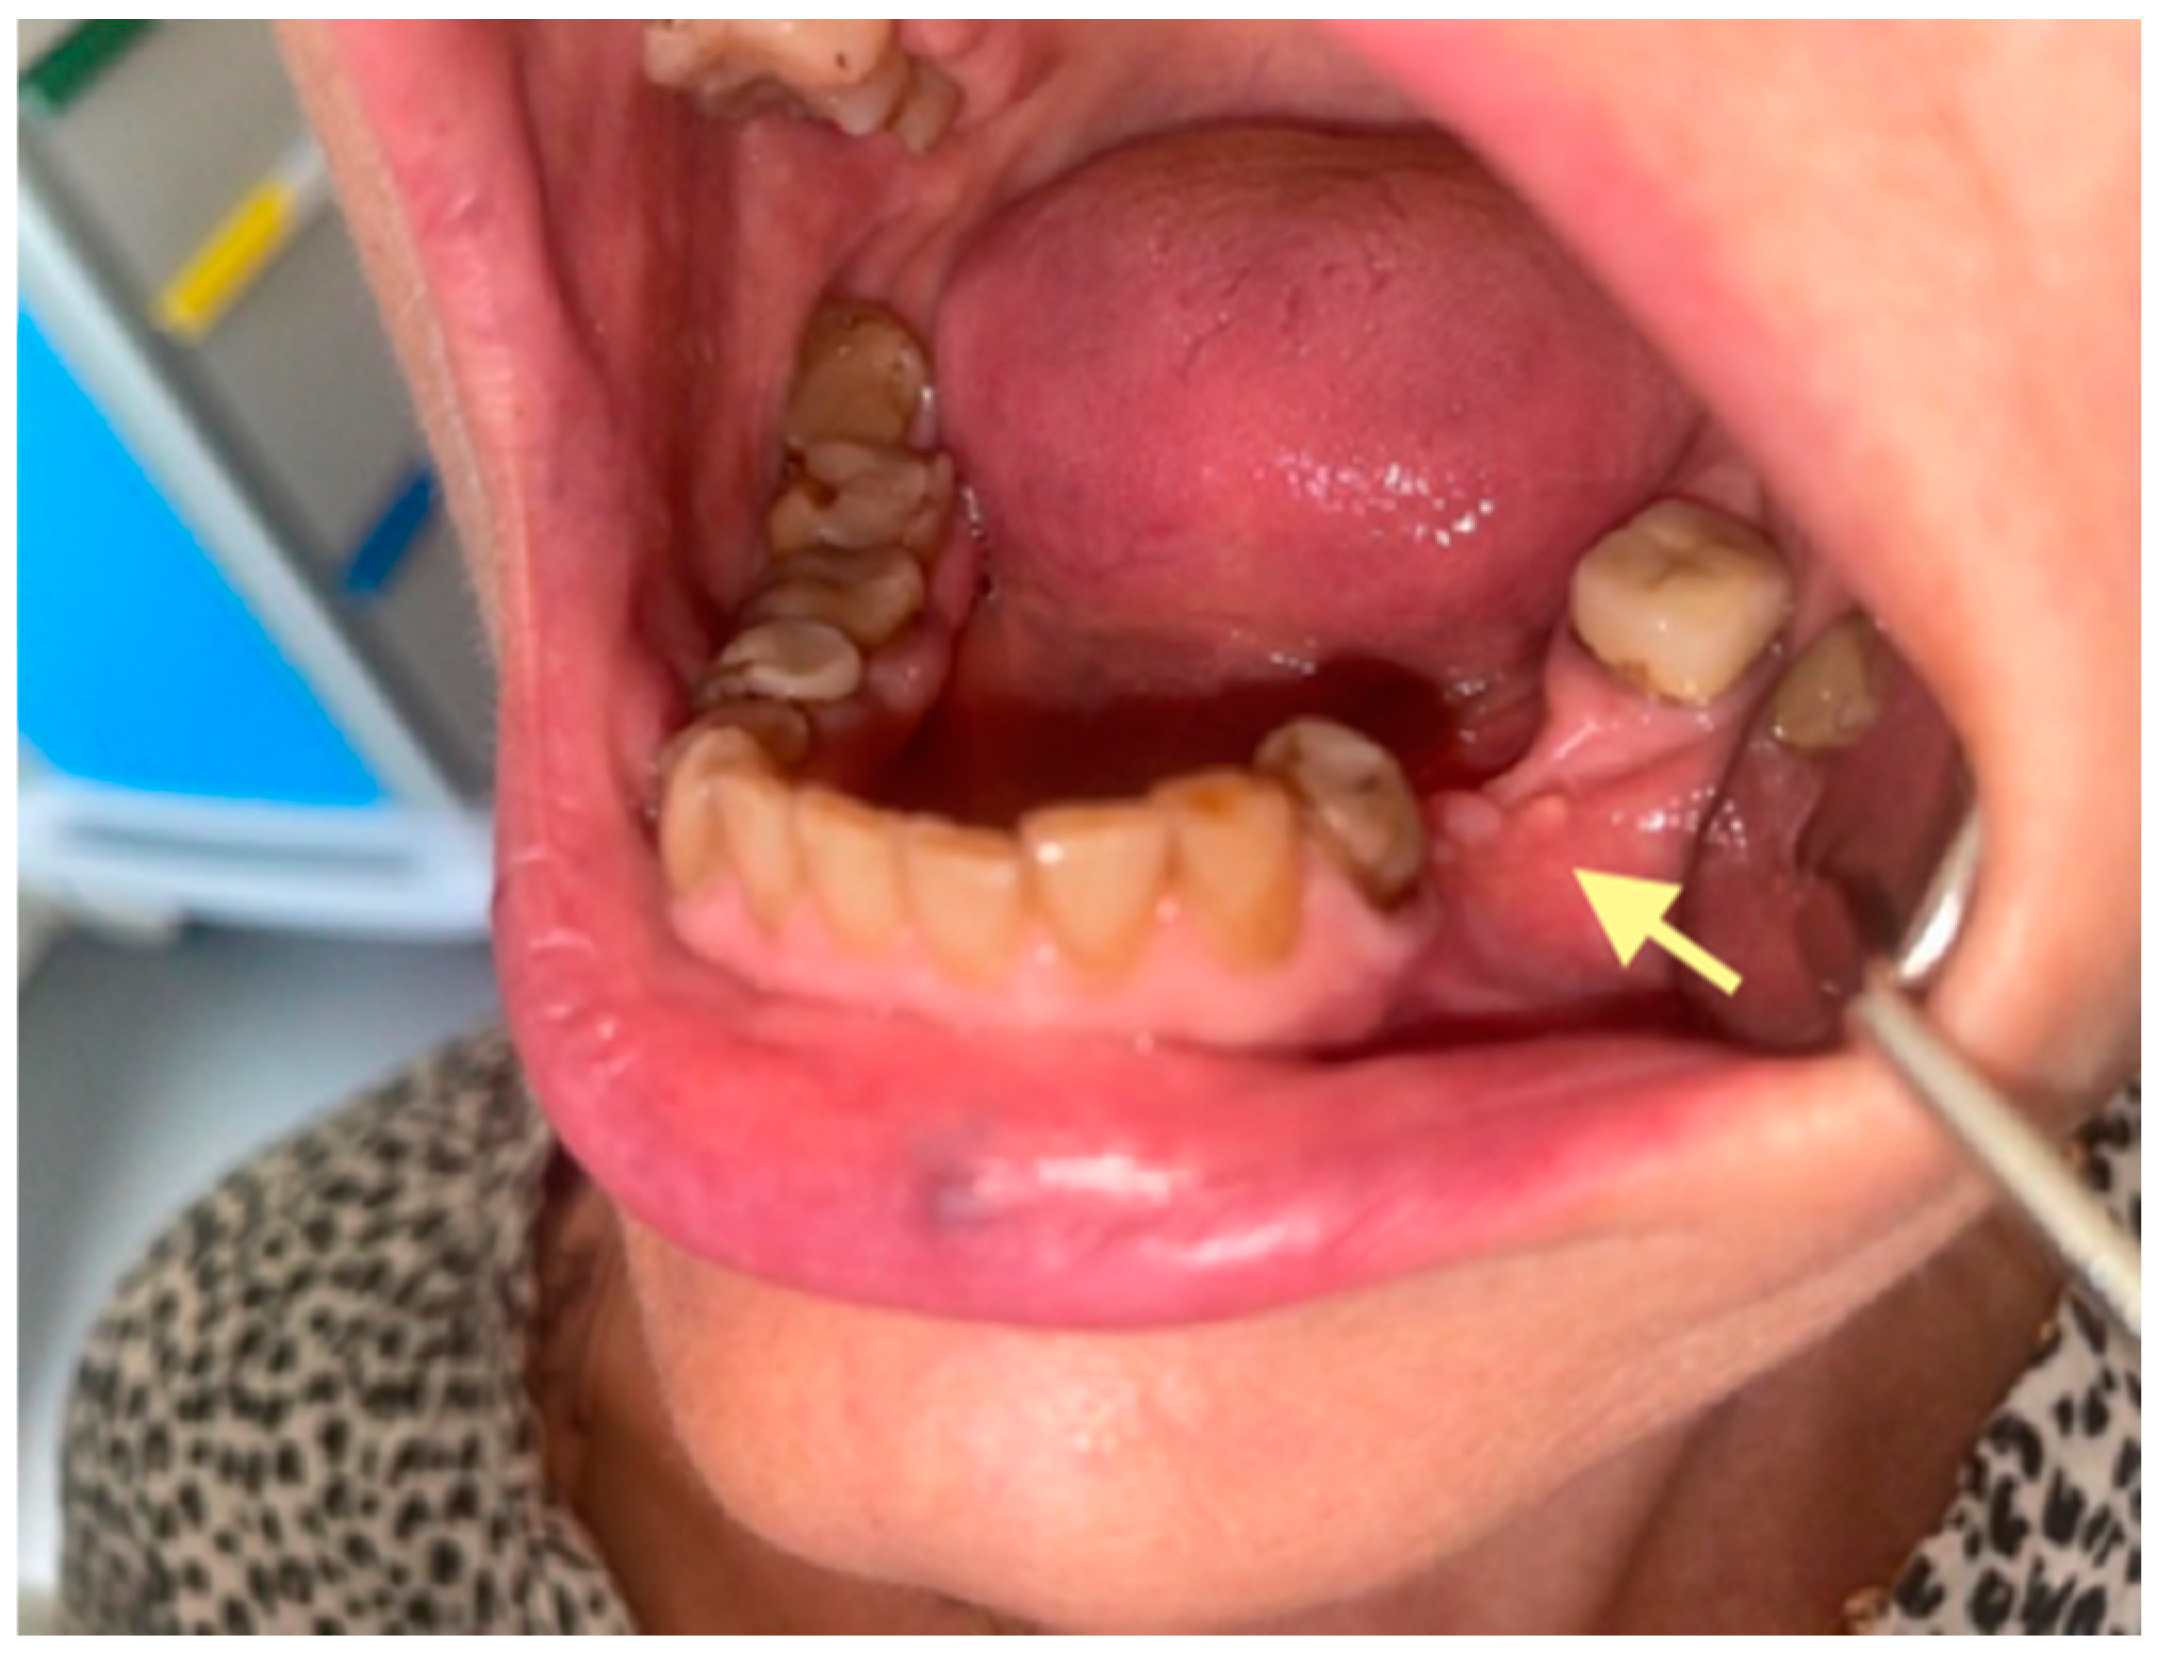

Figure 2.

Initial signs of osteonecrosis of the lower jaw in the area of the tooth 44 alveola (12 October 2024).

According to the classification of osteonecrosis of the jaws, the patient had stage I. Despite antibacterial therapy, an intraoral fistula formed. Therefore, in February 2025, an operation was performed (sequestrectomy with subsequent A-PRF placement).